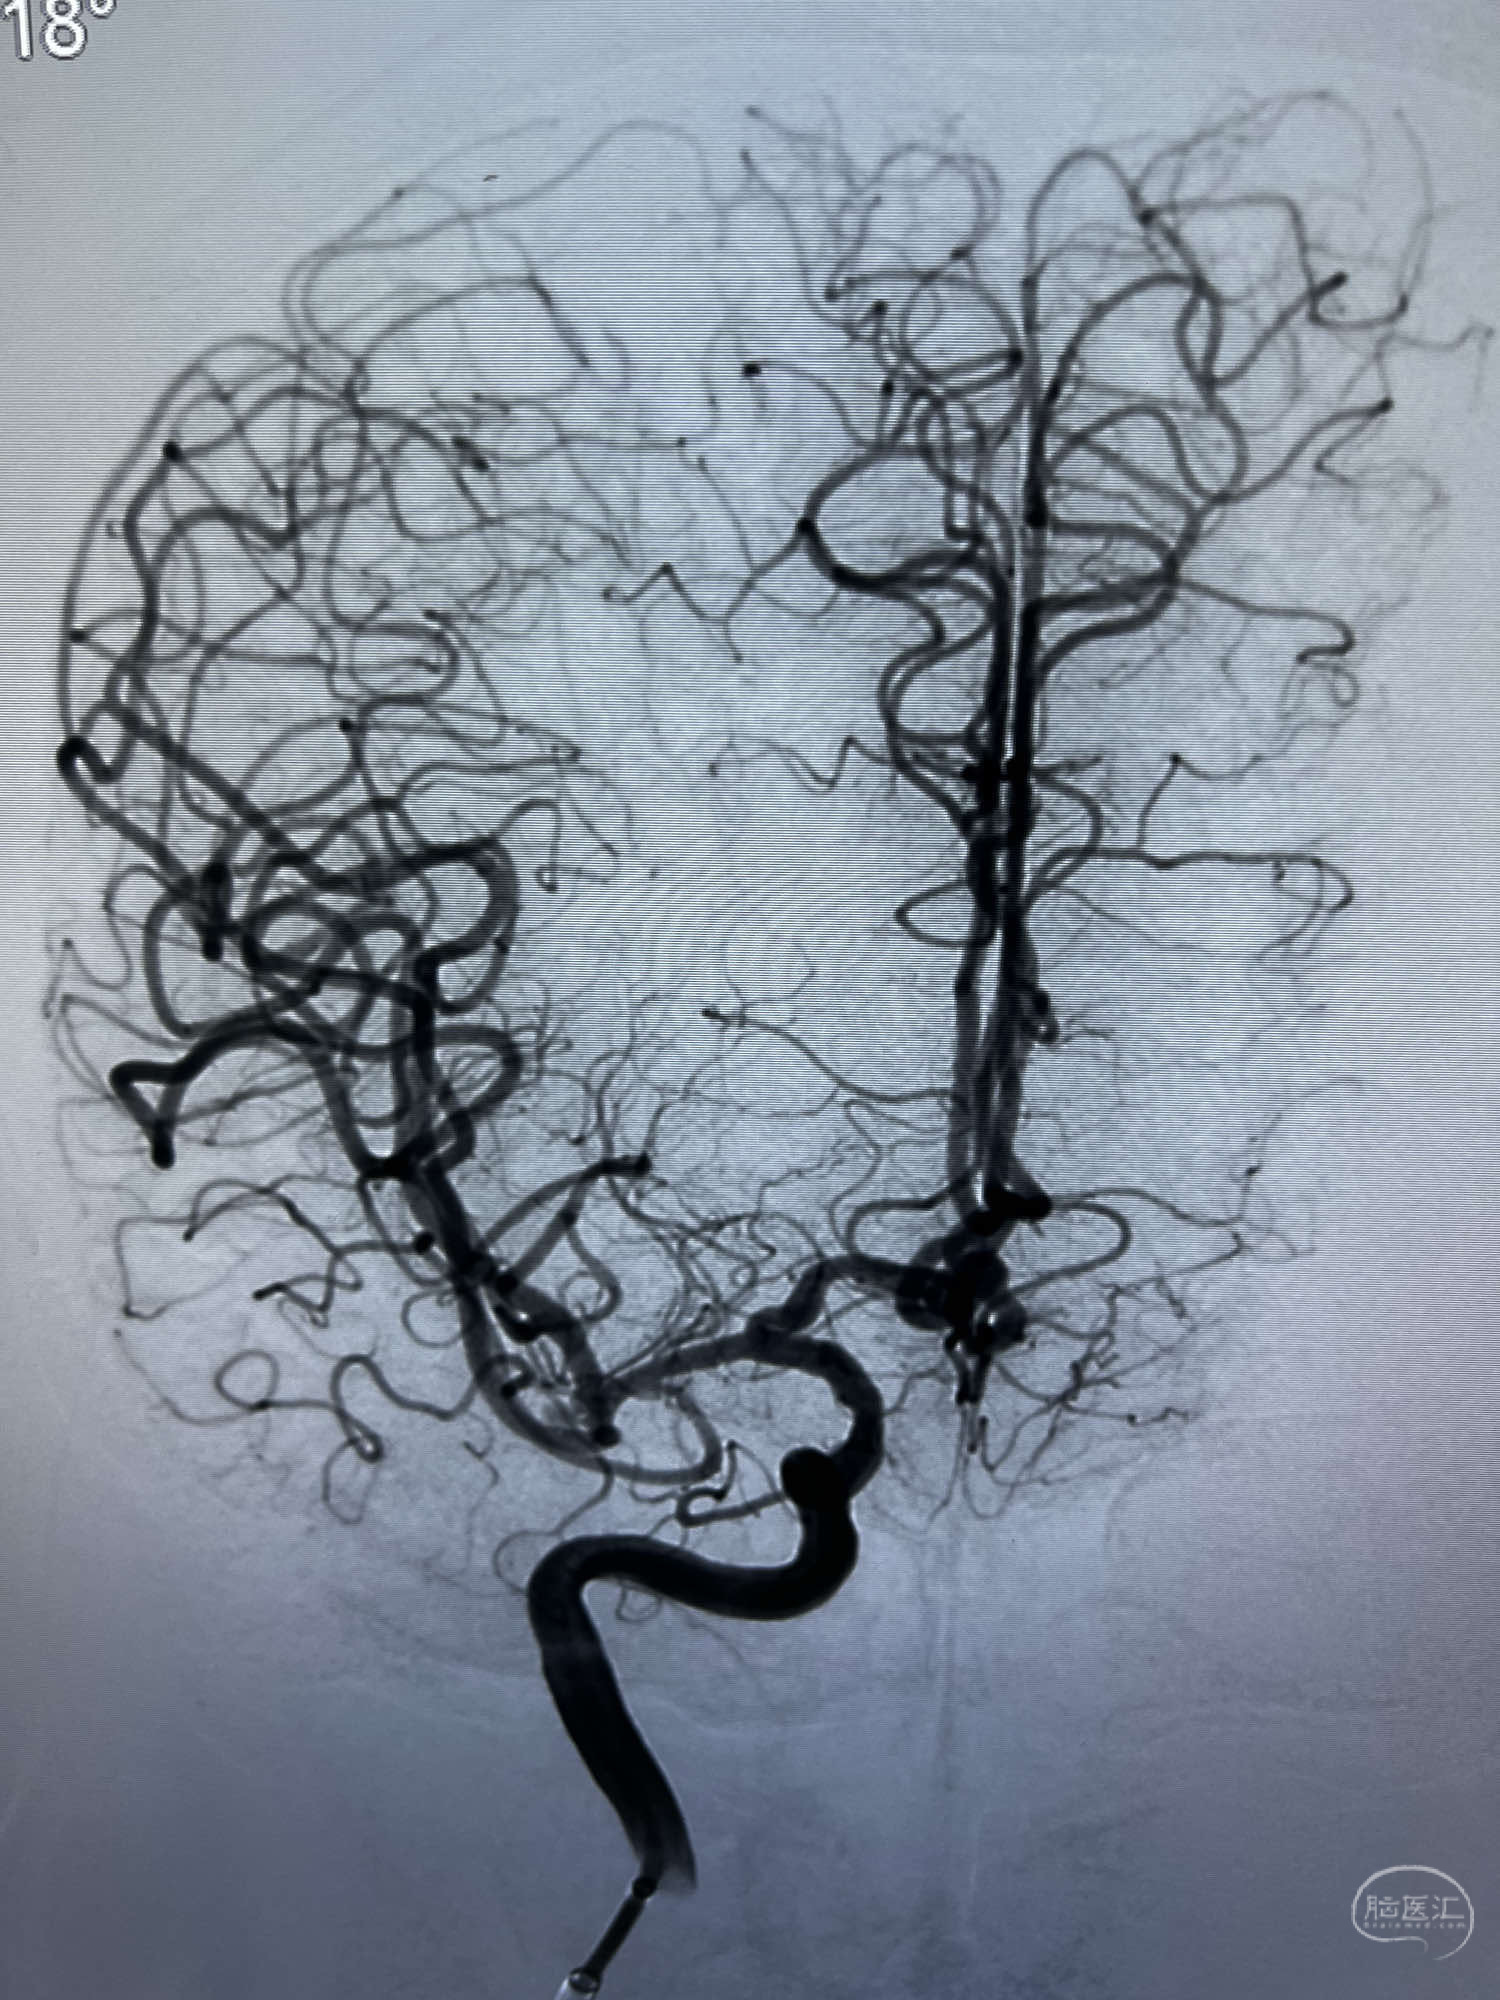

DSA示:左侧颈内动脉眼动脉段以远闭塞,后交通动脉开放,椎基底动脉通过后交通动脉代偿左侧大脑中动脉区域,右侧发出双侧大脑前动脉,右侧大脑中动脉M1末端宽颈动脉瘤,大小约4.3mmx4.6mm。

WEB瘤内扰流装置5mmx3mm经过“种子、萌芽、开花”三个阶段,打开后良好贴壁,动脉瘤内血液滞留,载瘤动脉通畅。WEB一步到位,通过瘤内扰流的方式起到栓塞动脉瘤的作用,避免了应用支架保护分支血管,简化了操作步骤,降低了术中血栓及出血的风险。